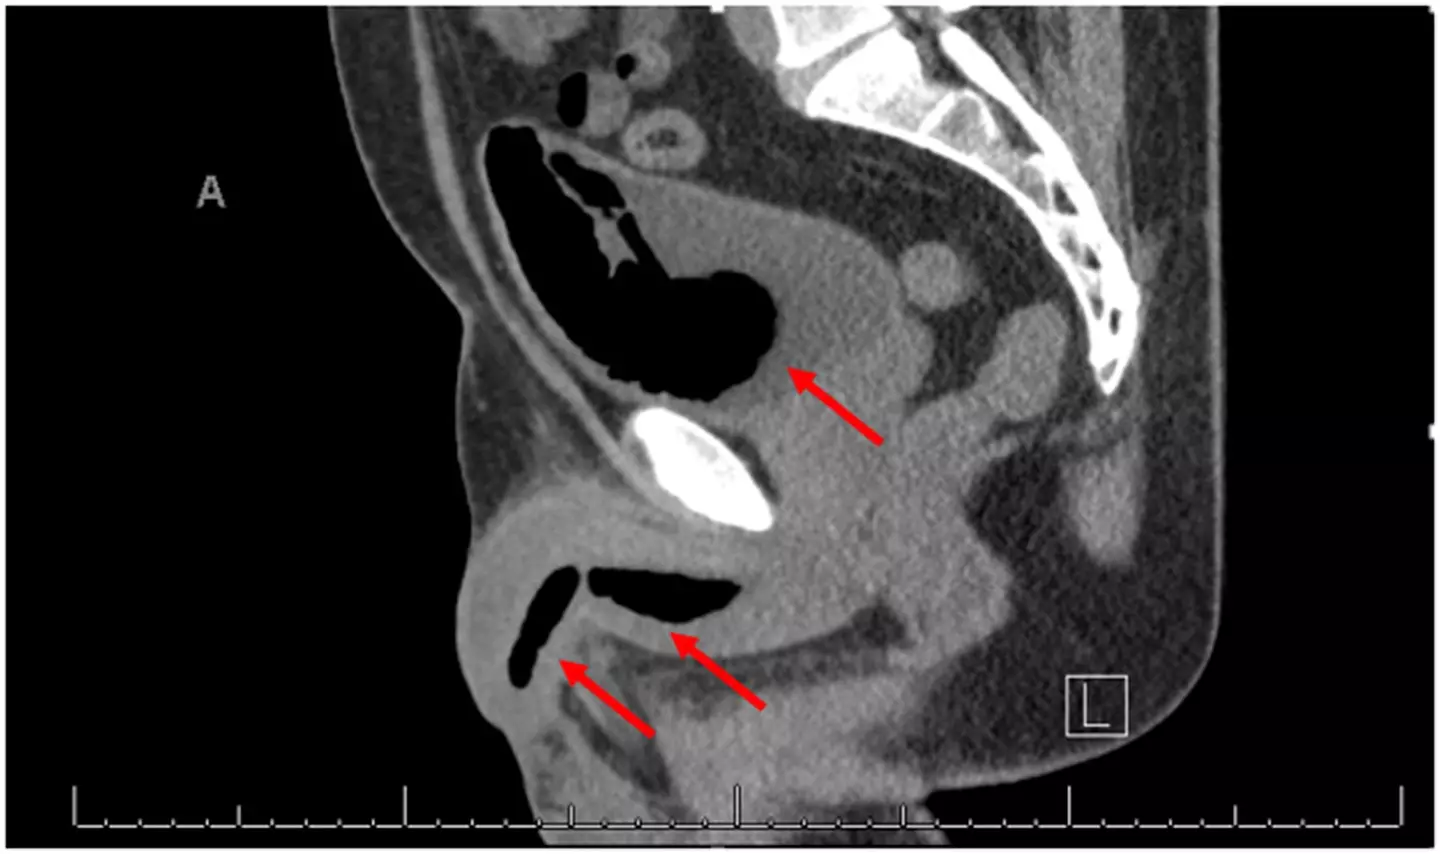

A computed tomography (CT) scan showed a hardened mass of foam in his bladder, measuring 10.7cm x 4.3cm x 6cm, and more in his penis, measuring 16mm in width.